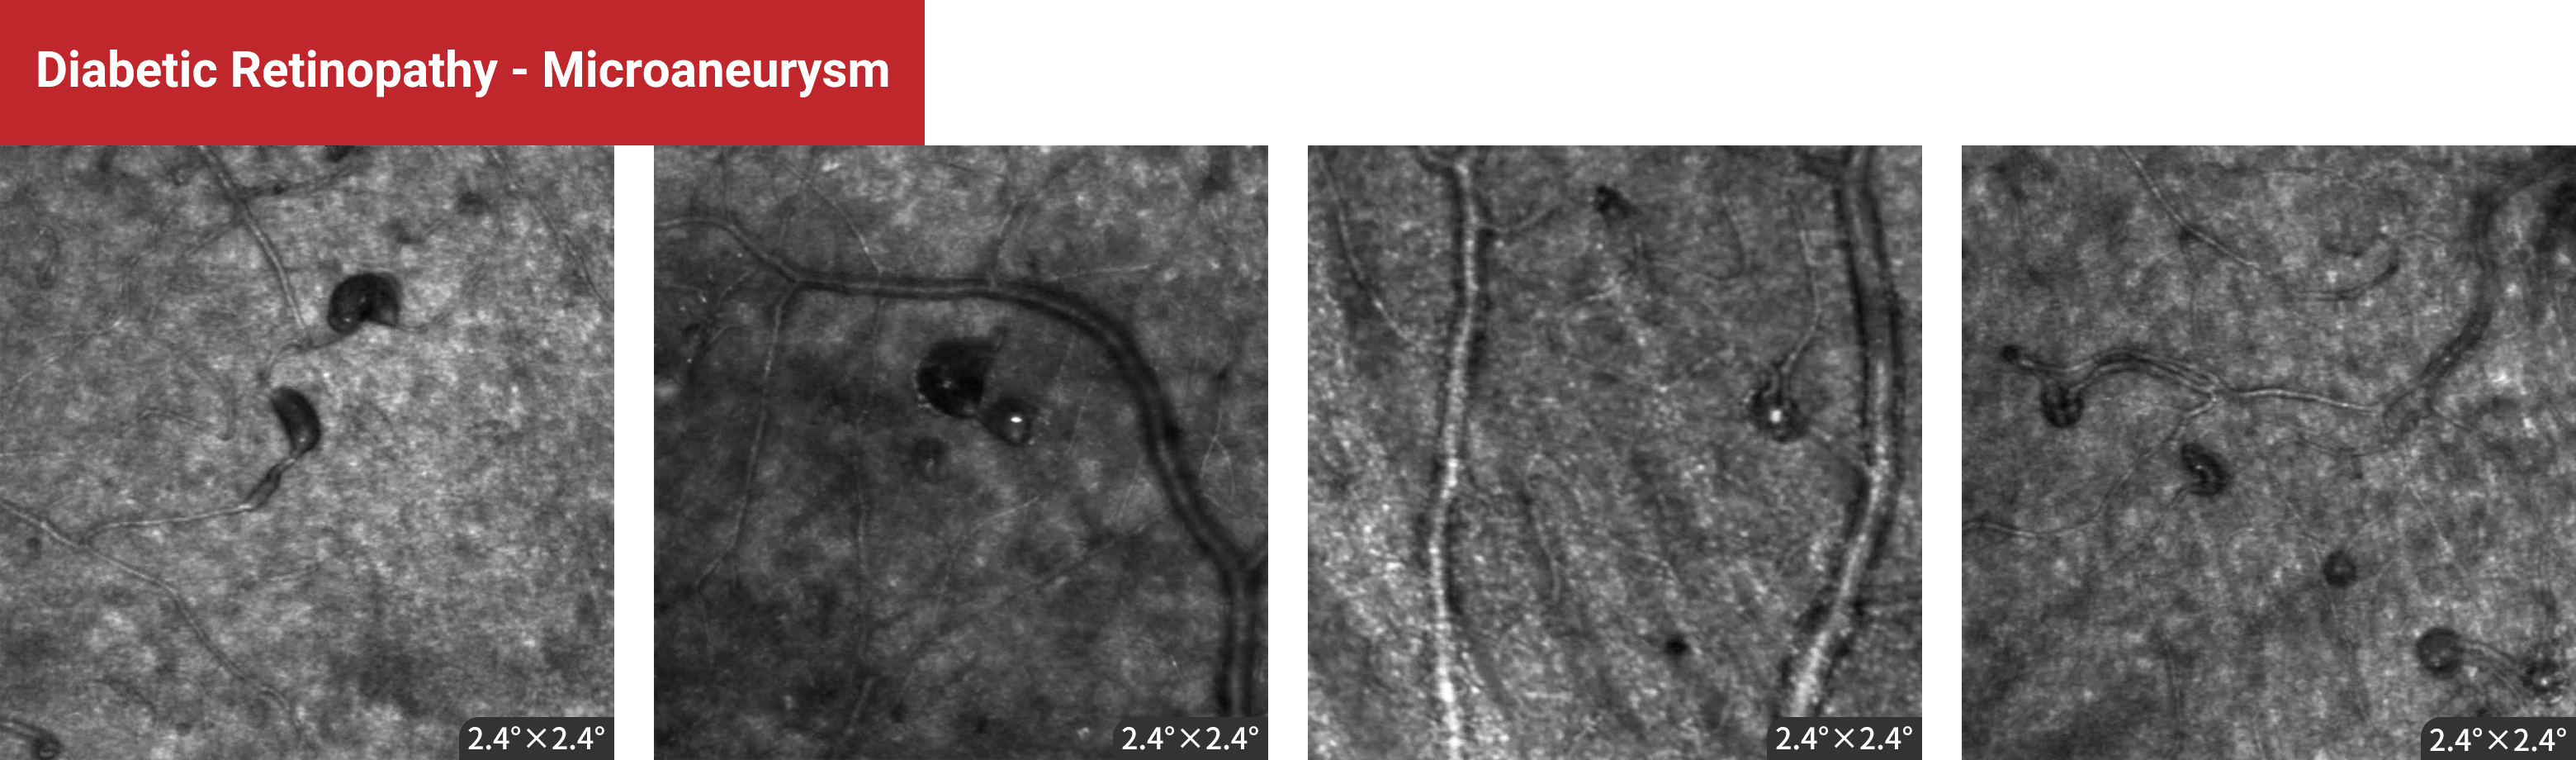

Diabetic Retinopathy - Microaneurysm